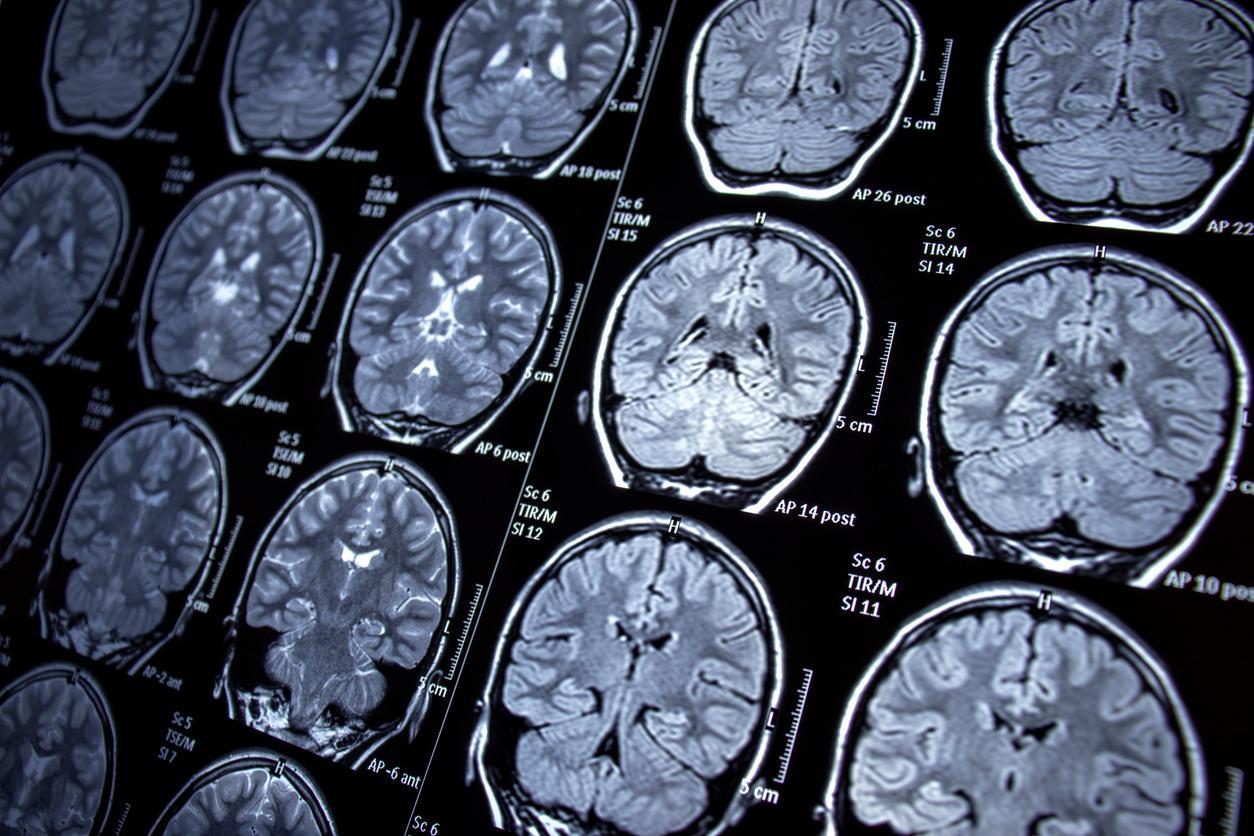

Dans une étude récente publiée dans la revue scientifique Cell Press Blue, les scientifiques se sont intéressés au rôle de ces cellules situées dans l’hypothalamus. Les tanycytes sont déjà connus pour assurer des échanges entre le système sanguin et le liquide céphalorachidien (LCR), qui circule dans le cerveau. Les chercheurs ont cherché à comprendre leur implication dans le transport de la protéine Tau, un biomarqueur clé dans le diagnostic de la maladie d’Alzheimer.

Chez une personne en bonne santé, les neurones libèrent cette protéine dans le liquide céphalorachidien, avant qu’elle ne soit ensuite éliminée dans le sang. En revanche, chez les personnes atteintes de la maladie d’Alzheimer, la structure de Tau se modifie. D'après l'Inserm, elle ne remplit alors plus correctement sa fonction à l’intérieur des neurones et s’accumule sous une forme pathologique dans le cerveau. Cette accumulation perturbe progressivement le fonctionnement cérébral et entraîne la dégénérescence puis la mort des neurones, responsables du déclin cognitif caractéristique de la maladie.

L'étude montre, à la fois chez l’animal et chez l’humain, que les tanycytes participent au transport de la protéine Tau du liquide céphalorachidien vers le sang. Il y est également révélé que la structure de ces cellules est altérée dans le cerveau de patients décédés des suites de la maladie.